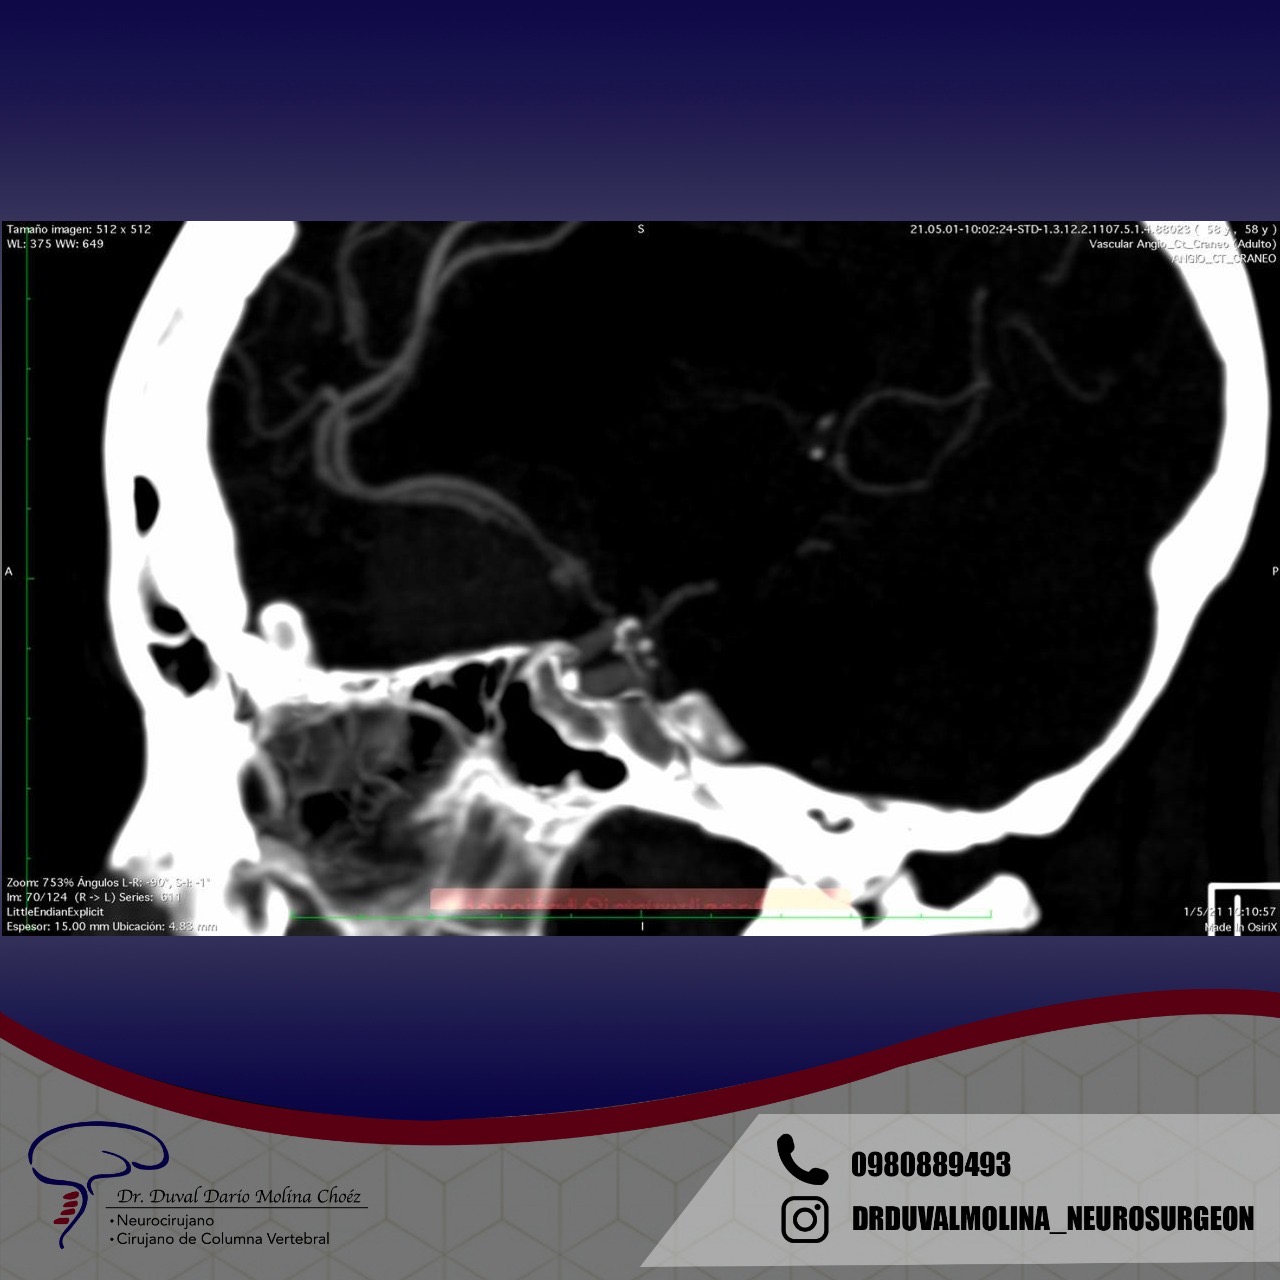

El patrón de hemorragia típico que se observa después de la ruptura de un aneurisma. La forma y la ubicación del aneurisma pueden predecir su comportamiento y también determinar qué opción de tratamiento es probable que sea la mejor. Alternativamente, si el aneurisma representa un bajo riesgo de ruptura o un alto riesgo quirúrgico, podemos optar por seguirlo con imágenes en serie. La intervención está diseñada para detener el flujo de sangre hacia el aneurisma, eliminando así el riesgo de hemorragia. Se puede realizar de forma endovascular rellenando el aneurisma desde dentro («coiling» endovascular), o mediante técnicas microquirúrgicas abiertas («clipaje»).

Clipaje (resolución) Quirúrgico

Se hace una pequeña incisión detrás de la línea del cabello y se extrae un trozo de hueso para permitir el acceso al aneurisma. Se identifica el aneurismabajo visión microquirúrgica, con sus ramas y uno o más clips aplicados externamente a su cuello. Cuando se cura el aneurisma, se reemplaza el hueso con placas especiales de titanio y se cierra la incisión.

Aneurisma clipado

Clip y soporte para aneurisma